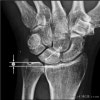

X-ray(PA view)에서 양성 척골 변이(positive ulnar variance)를 관찰할 수 있습니다.

X-ray : 척골 충돌 증후군(Ulnar impaction syndrome)